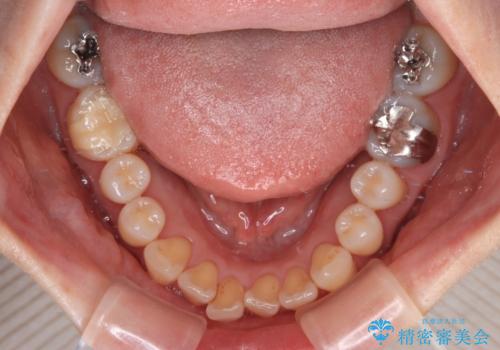

前歯のデコボコをインビザライン・モデレートで矯正治療

- 上下前歯のデコボコを気にして来院された患者様です。

安価なインビザラインパッケージを用いての治療を希望されており、デコボコの程度が中等度であったため、インビザライン・モデレートを用いて矯正治療を行うこととしました。

インビザライン・モデレートは、製作できるアライナーの枚数に制限があるため、移動可能な量に限りがあるものの、インビザライン・ライトよりも枚数が多いため、幅広い症例に対応可能です。